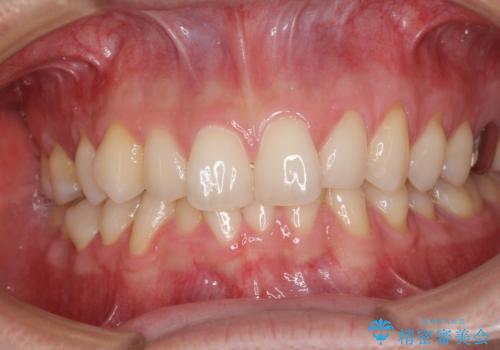

ディープバイトと叢生 インビザラインによる矯正治療

- 前歯のディープバイトと叢生を気にして来院された患者様です。

目立ちにくい装置を希望されていたため、ワイヤー装置とインビザラインを提案したところ、インビザラインを希望されました。

上下ともに叢生が認められたため、親知らずすべてを抜歯し、歯列全体を後方へ移動させることで歯列を整えることとしました。

ディープバイトもデコボコも改善され、気になっていた銀歯もセラミックとなり、患者様には大変満足していただきました。